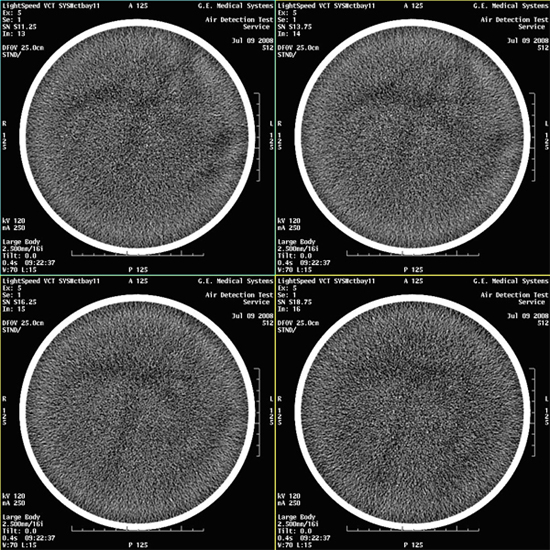

- Select VIEWER and review all images for

blotchy artifacts. (See Figure 1, Figure 2, and Figure 3). If an artifact is encountered, perform Tube Oil

Cooling System Air Removal.note:

If air artifact exists, the air activity may be more significant in Images 13 through 16, 29 through 32, 45 through 48, and 61 through 64.

Figure 2. Images with Marginal Air Artifacts